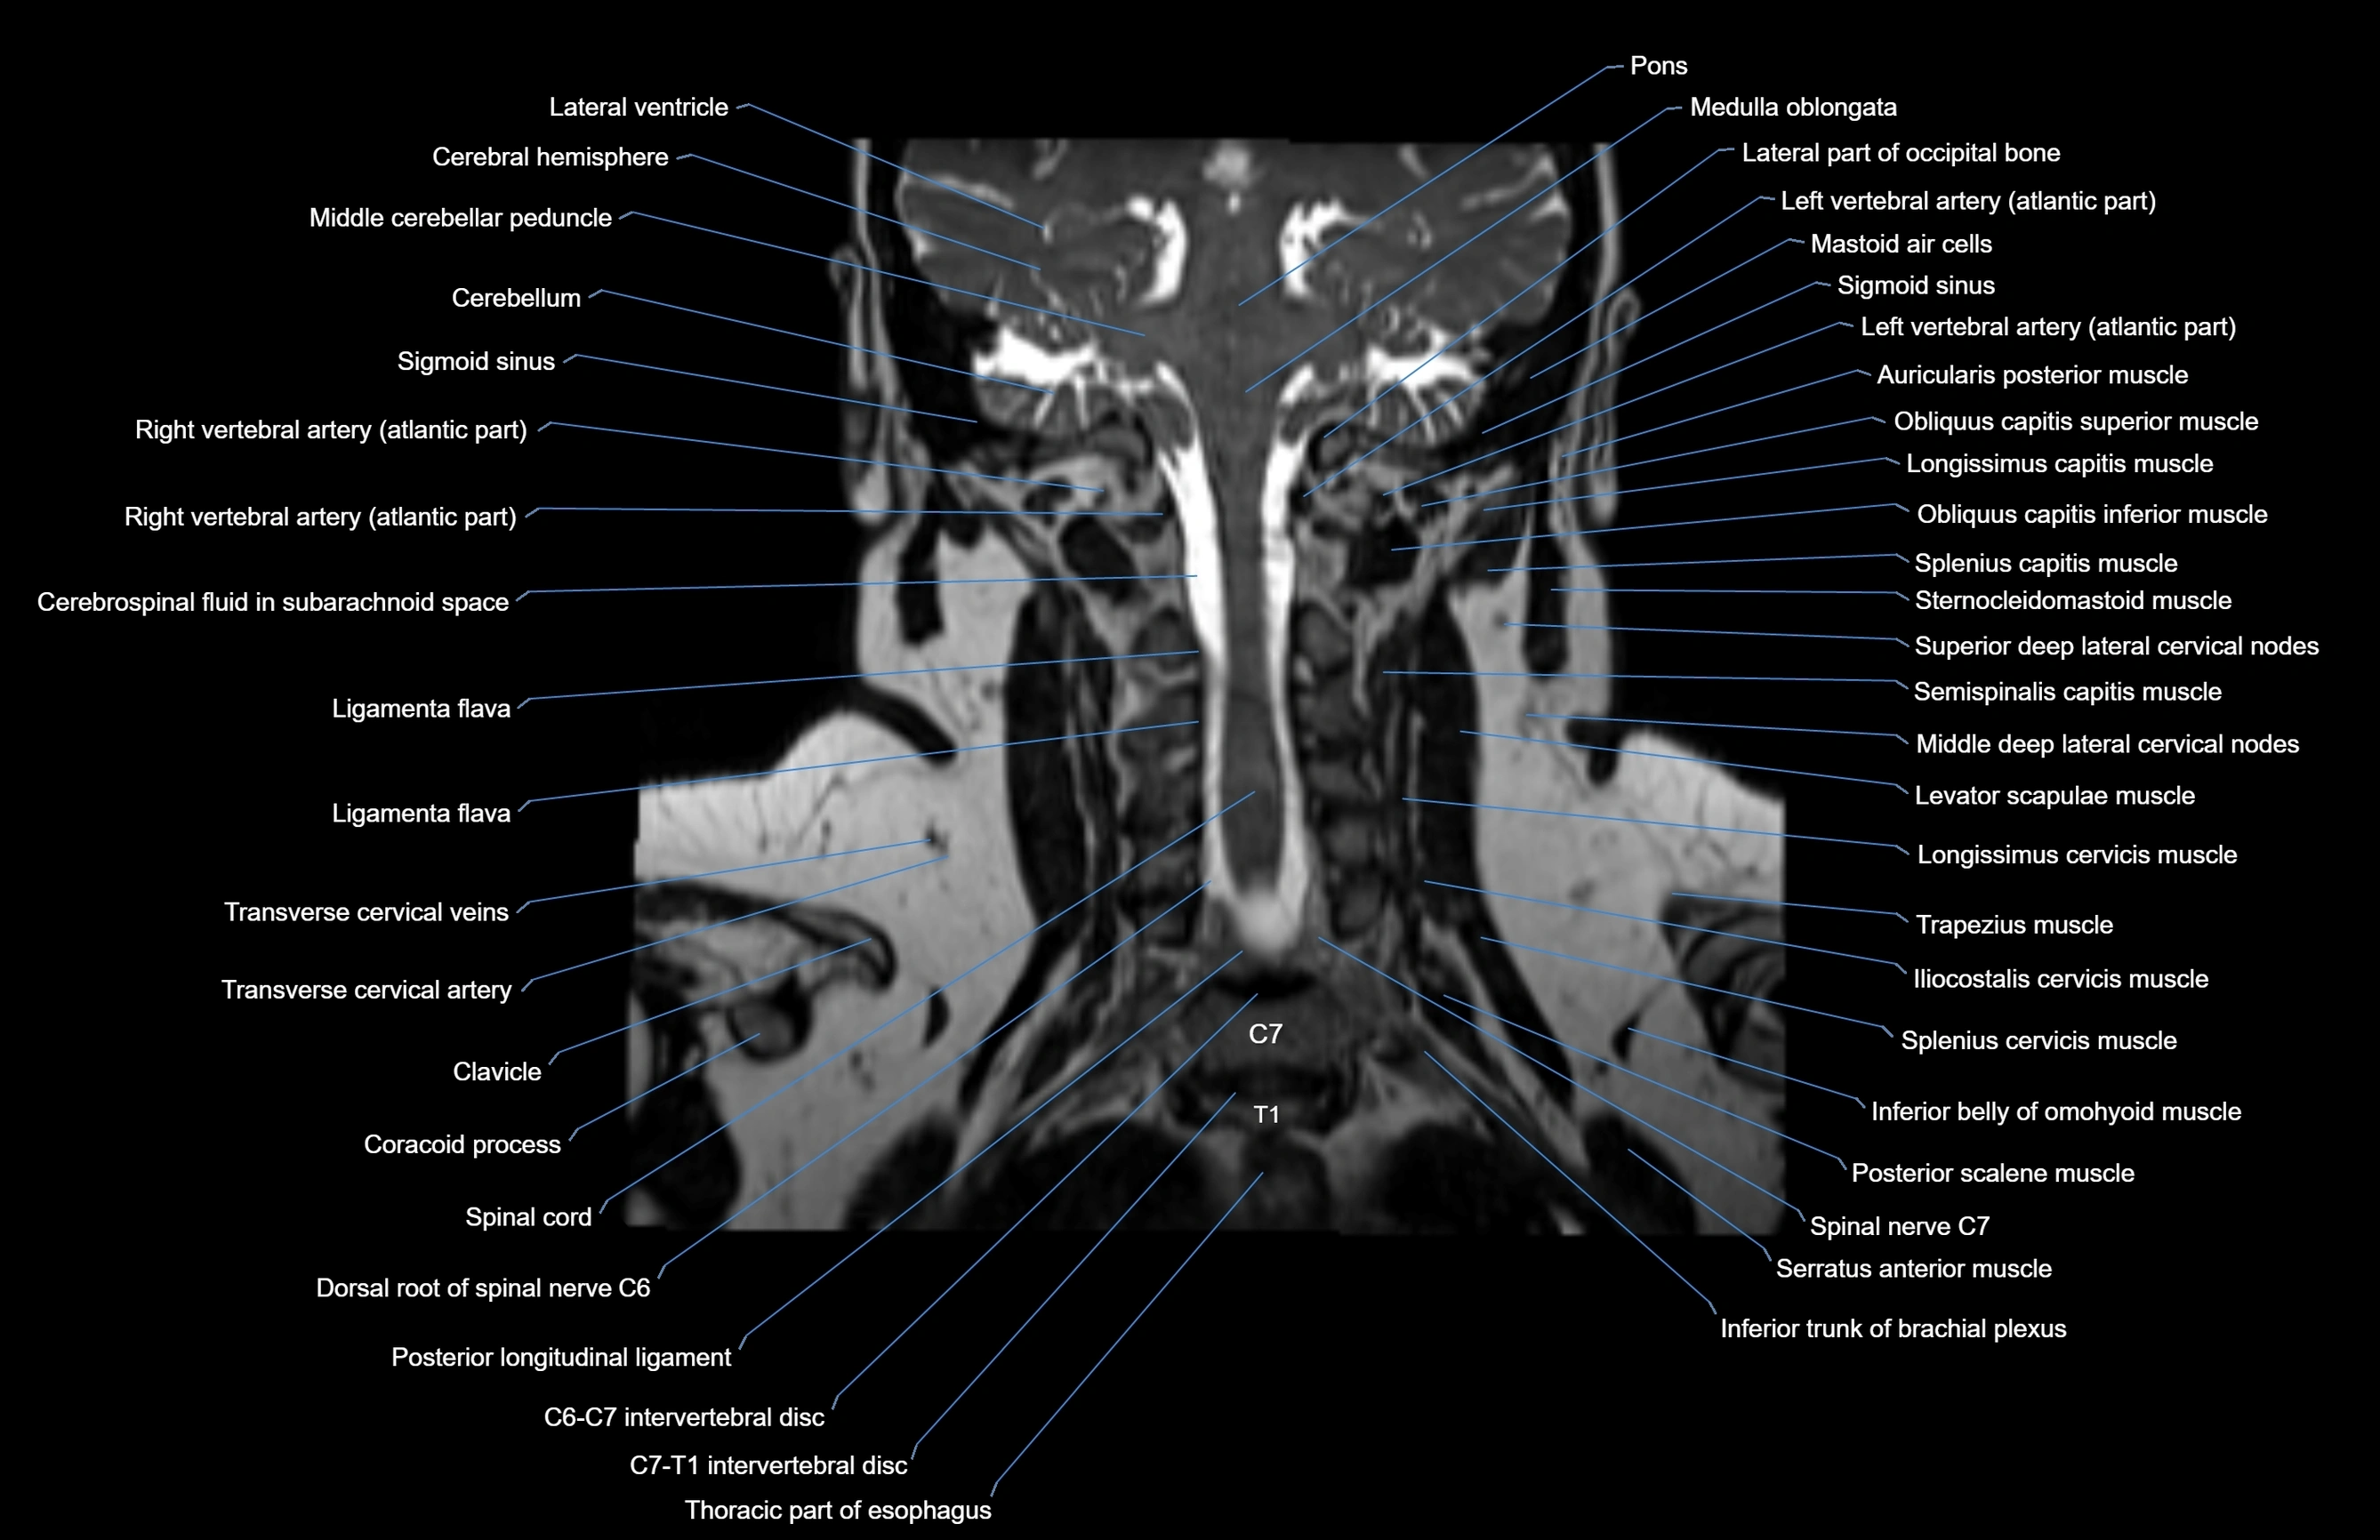

MRI images